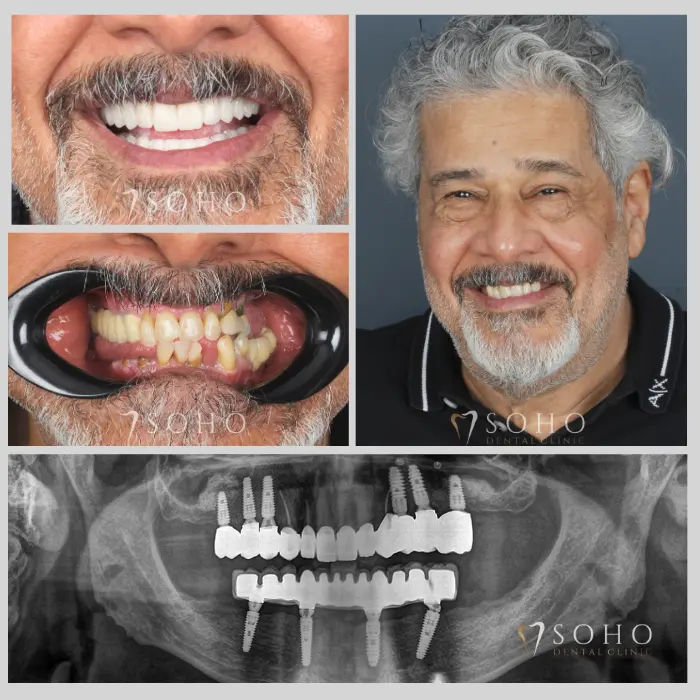

Real Patients. Real Smiles.

Explore the journey of our international patients through authentic visuals, elegant transformations, and moments captured inside Soho Dental Clinic. Let their stories inspire your own.

From First Visit to Final Smile.

Explore real patient stories captured in every transformation. These are more than smiles — they are renewed confidence, achieved with care and precision at Soho Dental Clinic.